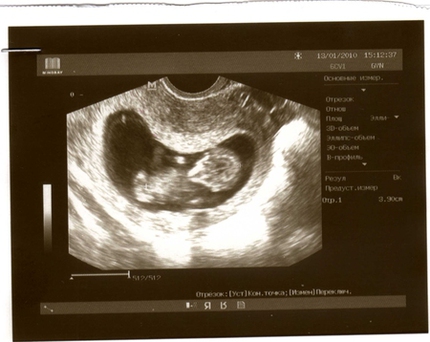

Здравствуйте.Месячные были 11.01.16,при задержке делала тесты на беременность и все положительные.В один прекрасный день начало кровить и мазало коричневыми выделениями,пошла к узисту,беременность не увидела,но сказала сдать анализ на хгч, сдала,первый результат 63.8,после трёх дней 324,после недели пошла снова на УЗИ и до сих пор не могут найти плодное яйцо